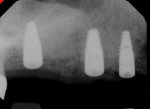

A 72-year-old male patient with a nonsignificant medical history desired implant placement in the upper right posterior area. The restorative dentist planned for a three-unit bridge and a single implant crown. After CBCT data were obtained (3D Accuitomo 170, J. Morita), implant planning software (Invivo6, Anatomage) was used to plan three implants (Straumann® Bone Level Implant, Straumann) for the maxillary right in restoratively driven positions (Figure 1). A surgical guide was then fabricated from that 3D generated planning (Figure 2). Once the patient was anesthetized, a full mucoperiosteal flap was reflected and the guide was seated intraorally, holding the flap out of the surgical field (Figure 3). The osteotomies were performed with a series of drills and corresponding keys (Straumann® Guided Instruments, Straumann) (Figure 4), which fit into the surgical guide sleeves and provided accurate drill placement to the planned depth from the pilot drill up to the drill of the final required diameter (Figure 5). After all of the osteotomies have been prepared, the guide can be left in place for the implants to be delivered through it, or it can be removed. In this case, once the final site preparations had been completed, the guide was removed (Figure 6), and the implants were placed directly into the osteotomies (Figure 7). Cover screws were then placed, and a posttreatment radiograph was acquired to evaluate the implant placement (Figure 8). After a 4-month healing period, the implants were uncovered, and temporary restorations were placed for a 2-month provisionalization period prior to final restoration (Figures 9 and Figure 10).